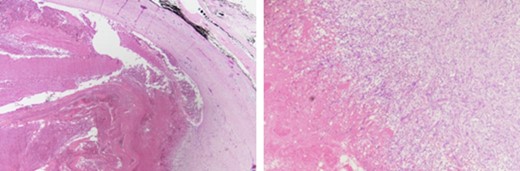

An excisional biopsy of the aneurysm was performed using a longitudinal incision in the skin at the level of the anterior border of the right sternomastoid muscle (Fig. 3). An excisional venotomy was also performed, and a whole aneurysmal wall excision done. Finally, the internal jugular vein was closed using a 5.0 Proline suture. Hemostasis was accomplished, and the specimen was sent for histopathological examination. A histopathological examination of the mass showed a cystic structure containing organizing blood clots surrounded by a thick fibrous wall, suggestive of an organizing thrombosis (Fig. 4).

A histopathological examination of the mass showed a cystic structure containing organizing blood clots surrounded by a thick fibrous wall, suggestive of an organizing thrombosis.